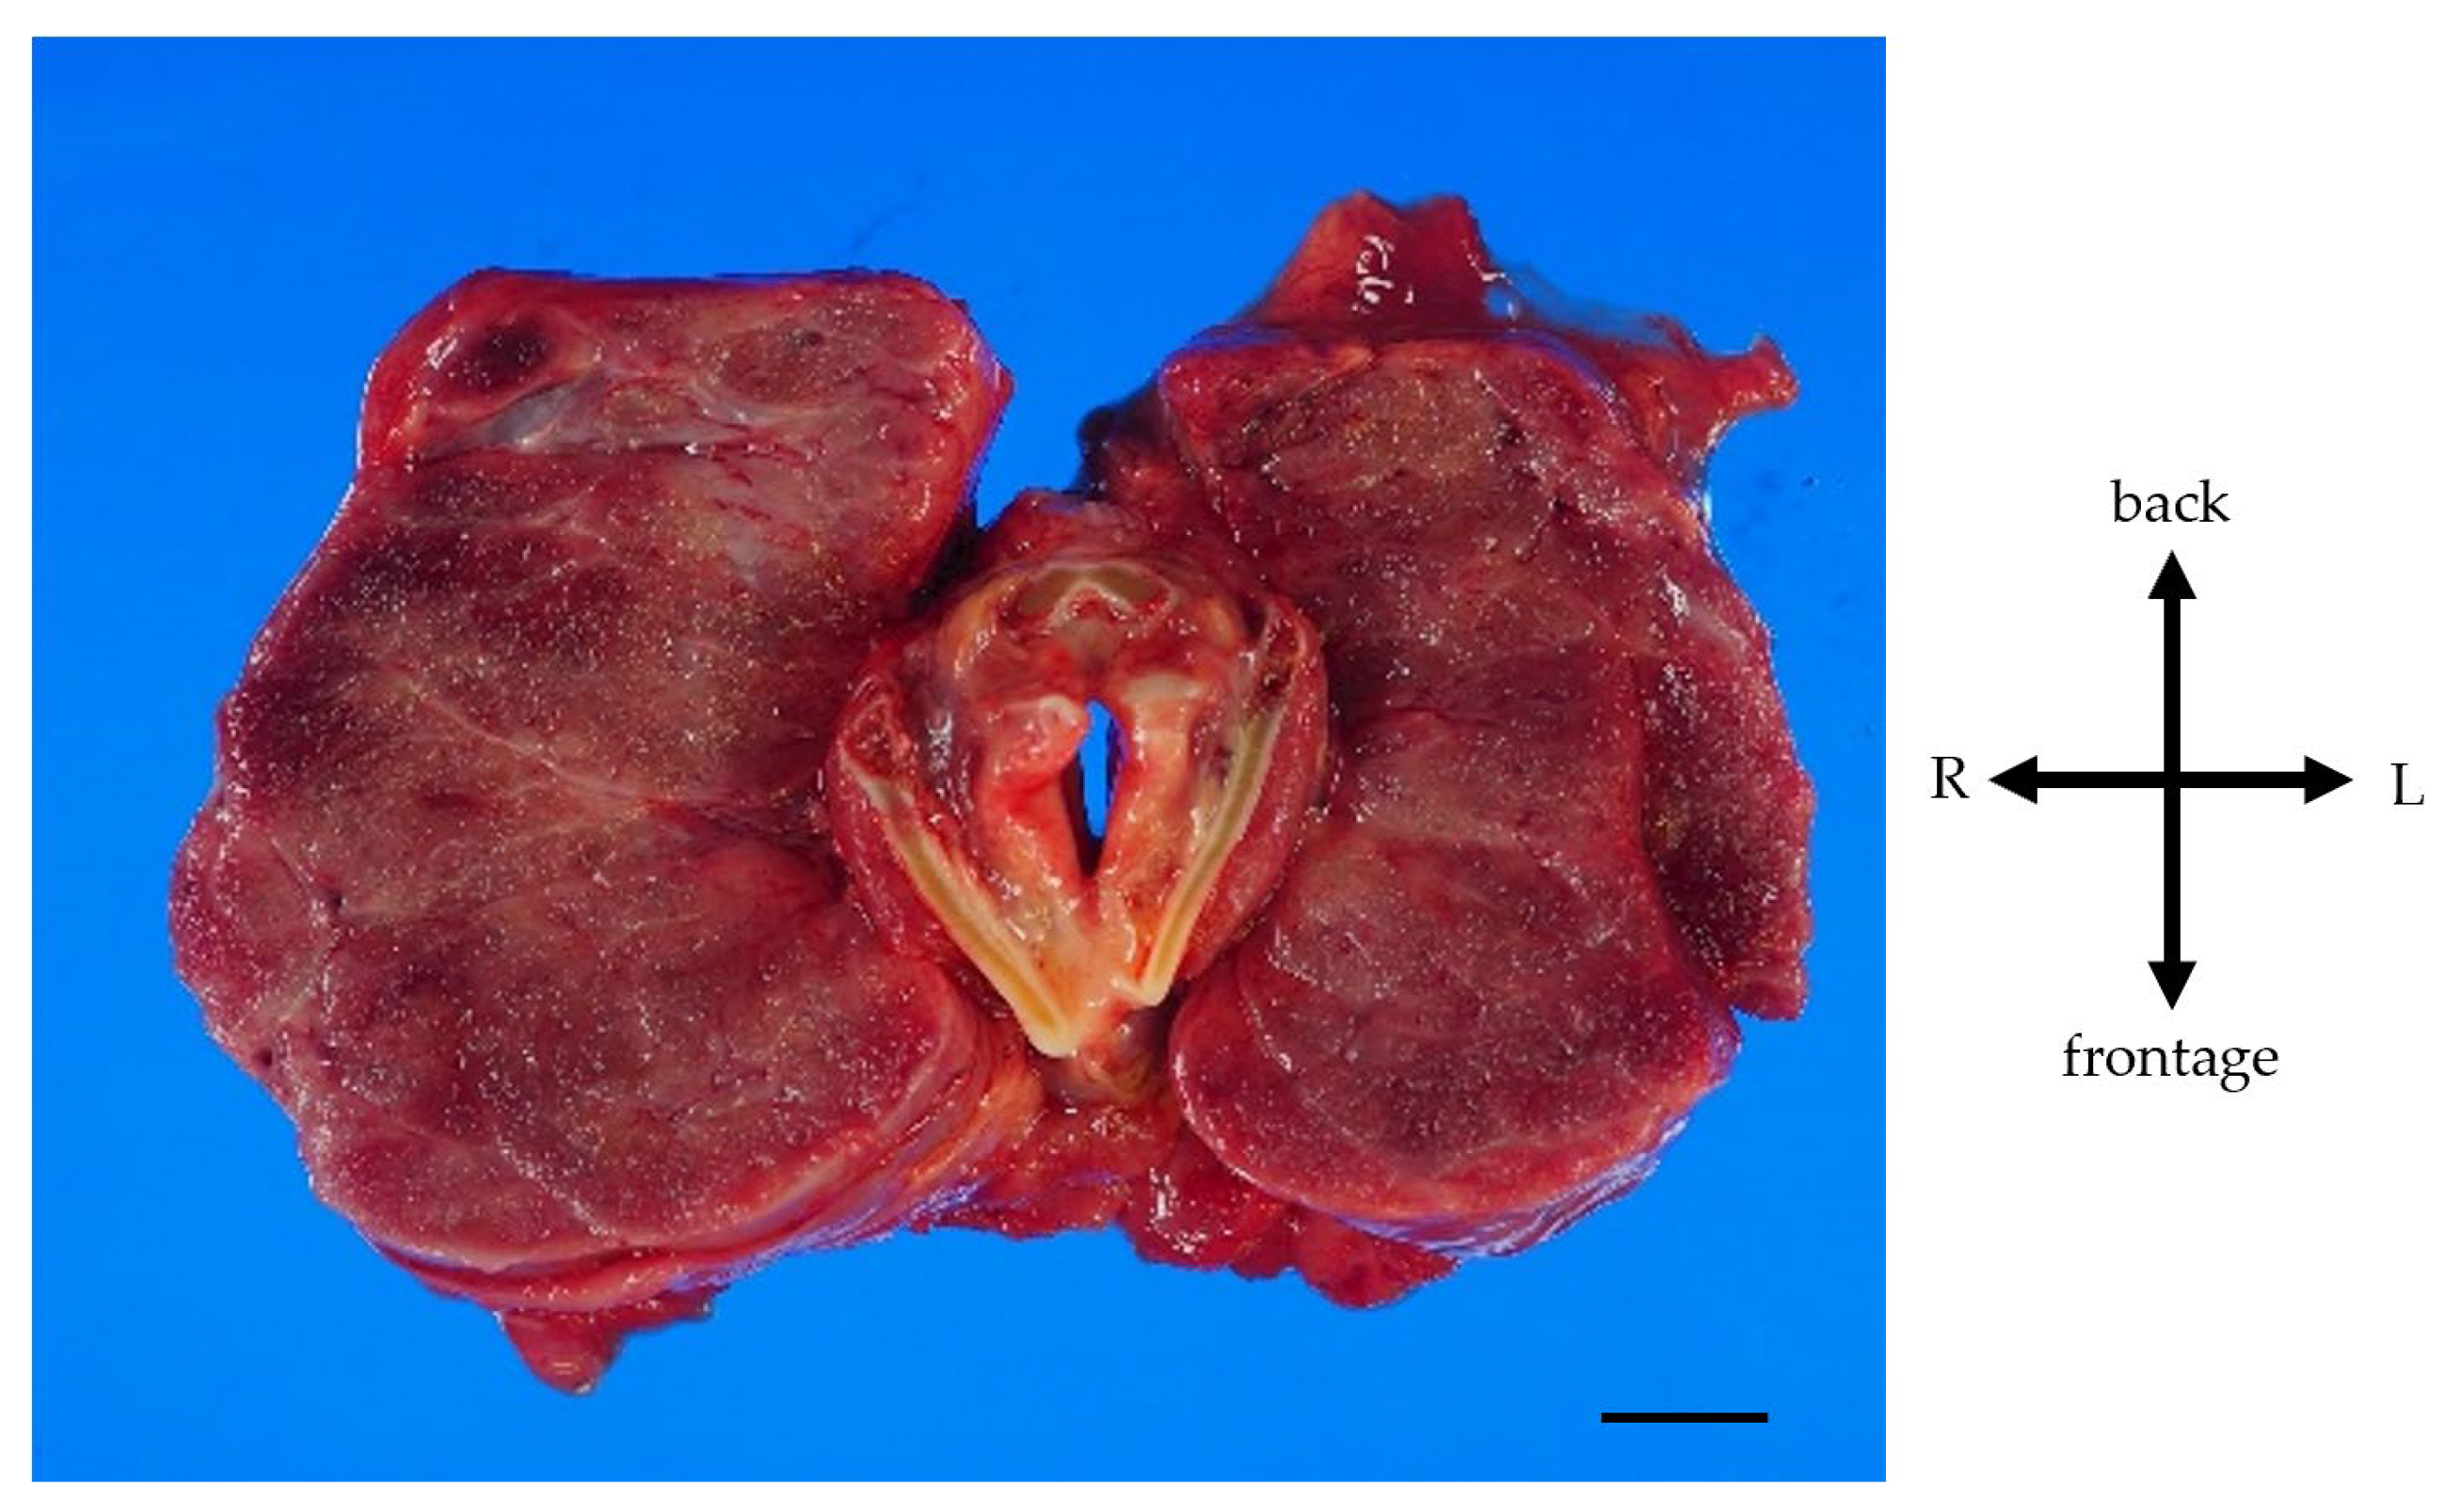

A pathological autopsy was performed. The gross thyroid findings included diffuse enlargement (weight 675 g, size 14 cm × 6 cm, normal weight 20~30 g, normal size 5 cm × 2.5 cm) and compressive constriction of the upper airway by the thyroid gland (Figure 4).

Figure 4.

Gross findings of goiter. Weight of the goiter was 675 g. Size of the goiter was 14 cm × 6 cm. The thyroid gland is symmetrical and diffusely enlarged. Pressure–drainage stenosis of the trachea due to the giant goiter was present. Scale, 1 cm.

There were no obvious malignant findings. Regarding other gross findings, the bilateral main pulmonary arteries were dilated, and the lung weights were increased (right 1030 g, left 1110 g, normal weight of right lung for women 200~500 g, and that of left lung 200~400 g). The right ventricle and atrium were also dilated. Significant right heart hypertrophy was observed. These findings suggested chronic pulmonary hypertension. The cause of death was considered to be respiratory failure by airway narrowing due to thyroid gland enlargement, which was caused by continuous intravenous epoprostenol therapy for IPAH.